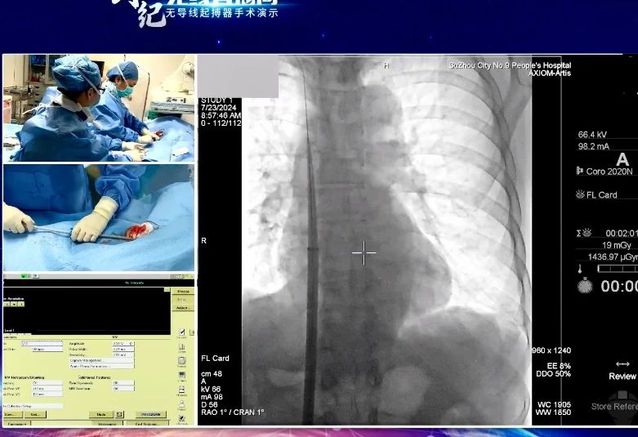

7月24日,“创势纪·无线直播间—苏皖区域无导线起搏器手术演示”在线上举行,探花直播 心血管内科主任吴雁鸣参与手术演示,助力提升区域心血管病防治水平。本次活动由江苏省医学会心血管病学分会副主任委员、苏州市心血管病学分会主任委员、苏州大学附属第一医院心内科主任蒋廷波主持,汇聚了一大批专家教授开展手术演示和线上探讨,通过学术交流积极推动苏皖地区心血管病防治水平的进一步提高。

早在2021年,探花直播 心血管内科就积极引入和开展无导线心脏起搏器植入术,是我区首家成功独立开展无导线起搏器植入手术的医院。心血管内科主任吴雁鸣是我区首位独立无导线起搏器术者,目前已成功独立植入近30例,受益人群大多为高龄老人,其中年龄最大的患者接受手术时已经103岁。